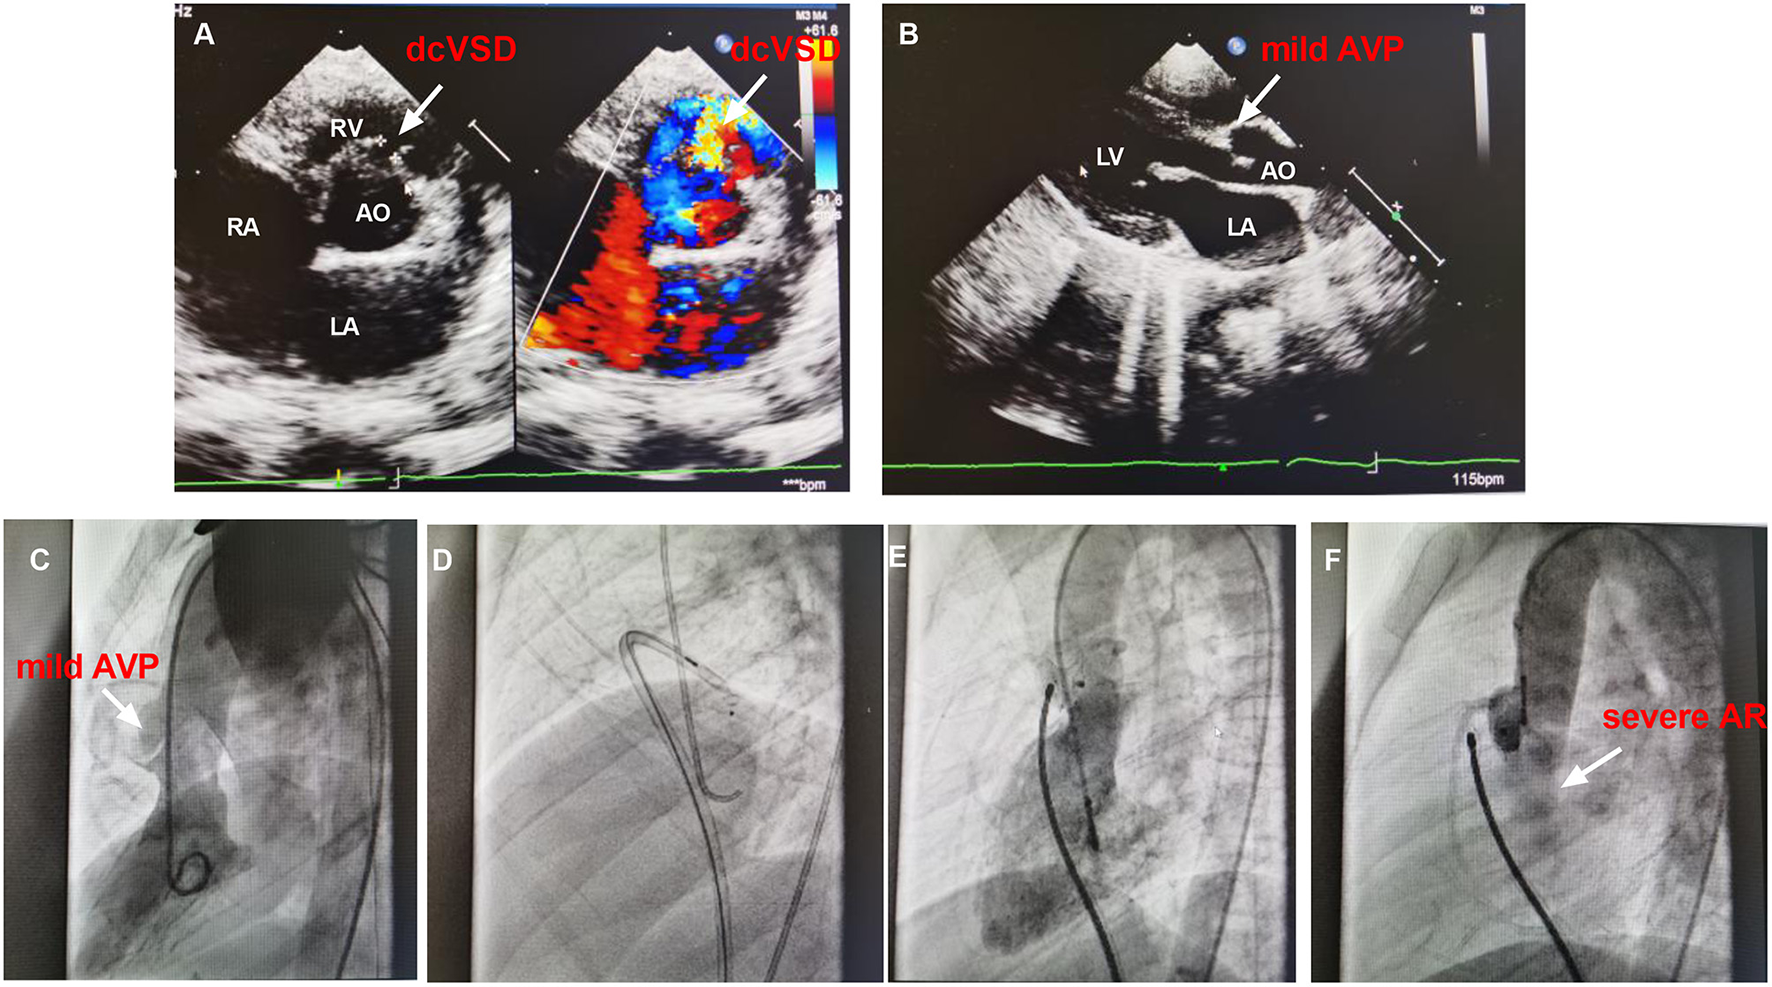

The failed case 12 was an 8.3-year-old male weighing 24.0 kg with a complaint of heart murmur of 3/6 grades. TTE before closure revealed a 5.0 mm sized dcVSD with a left to right shunt, mild AVP, and left atrium enlargement (25 mm) (Figures 4A,B). The defect measured 2.0 mm on left ventricular angiography and mild to moderate AVP was observed (Figure 4C). A 4/4 mm sized ADO-II was initially chosen (Figure 4D). After the establishment of the arterial–venous loop, the delivery sheath was advanced into the LV. First, the left disk was pushed out of the sheath and then the delivery system was pulled back gently. However, when we tried to release the waist and right disk of the device, both the delivery system and the occluder slid to the right ventricle immediately and easily. Thereafter, we re-analyzed the left ventricular angiogram and found that the size of dcVSD was greatly underestimated because of the AVP. The size of the defect was re-measured as large as 8.0 mm. A symmetrical double-disk occluder (SHAMA, Shanghai, China) sized 10 mm was used to close the defect (Figure 4E). However, before the deployment of the occluder, both the aortic root angiography and TTE revealed moderate to severe AR (Figure 4F). At last, the occluder was withdrawn and the patient was transferred to the cardiac surgery department in West China hospital for surgical closure of dcVSD.

Figure 4

The images of TTE and angiography of case 12. (A,B) shows the dcVSD and the mild AVP on TTE. (C) Shows the mild AVP by left ventricular angiography. (D) Demonstrates the closure using ADO-II and (E) Shows the closure with symmetrical double-disk occluder. (F) Shows the AR after deploying occluder. AO, aorta; AR, aortic regurgitation; AVP, aortic valve prolapse; dcVSD, doubly committed subarterial ventricular septal defect; LA, left atrium; LV, left ventricle; RA, right atrium; RV, right ventricle; TTE, transthoracic echocardiography.